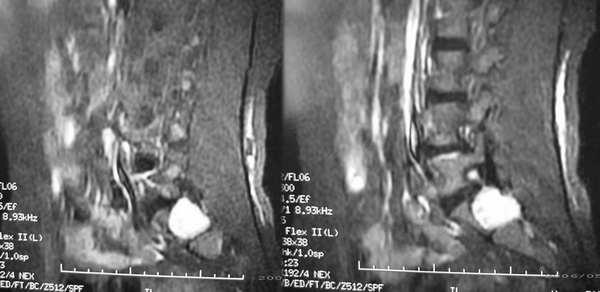

患者,女性,60岁。腰痛、腿痛一周余,临床医生考虑:椎间盘突出,行ct及mr检查

病灶为长t1长t2信号,对s1椎体是压迫吸收,应首先考虑骶管囊肿。建议增强扫描。

征象:1、骶椎管偏右侧囊性病变,长t1长t2改变,均匀。2、慢性病变过程,邻近骨质有吸收变薄。

考虑:盲囊蛛网膜囊肿。

S1椎长T1长T2信号,与蛛网膜下腔相连,边界清晰,CT可见局部骨质吸收,边缘硬化改变。支持骶管囊肿。